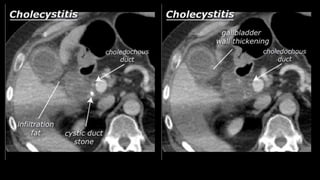

• Bile stones

• Bile stones may develop in the gallbladder

(cholecystolithiasis) and may migrate to the

bile ducts (choledocholithiasis). Bile stones

are generally invisible on CT scans.

Ultrasound is most suited to identify bile

stones. However, the consequences of an

obstructive bile stone can be seen on CT. The

obstruction prevents the bile from passing.

With an obstructive stone in the gallbladder,

the gallbladder becomes enlarged

(hydropic). With an obstructive stone in the

bile ducts, the bile ducts are dilated; the

intrahepatic bile ducts are dilated when

their diameter exceeds 2 mm, the

choledochous duct is dilated when its

diameter exceeds 6 mm

• Cholecystitis • Acomplication of bile stones is an infected gallbladder or cholecystitis. Cholecystitis rarely occurs in the absence of bile stones. Ultrasound is also best suited to diagnose cholecystitis. Ultrasound improves the visibility of the bile stones, and gallbladder compressibility can be evaluated (dynamic examination). Absent compressibility constitutes a key characteristic of cholecystitis (see abdominal ultrasound class). Other characteristics of cholecystitis on CT include gallbladder wall thickening and infiltration of the fat surrounding the gallbladder. A common complication of cholecystitis is gallbladder perforation, where bile leaks into the abdominal cavity (biloma).